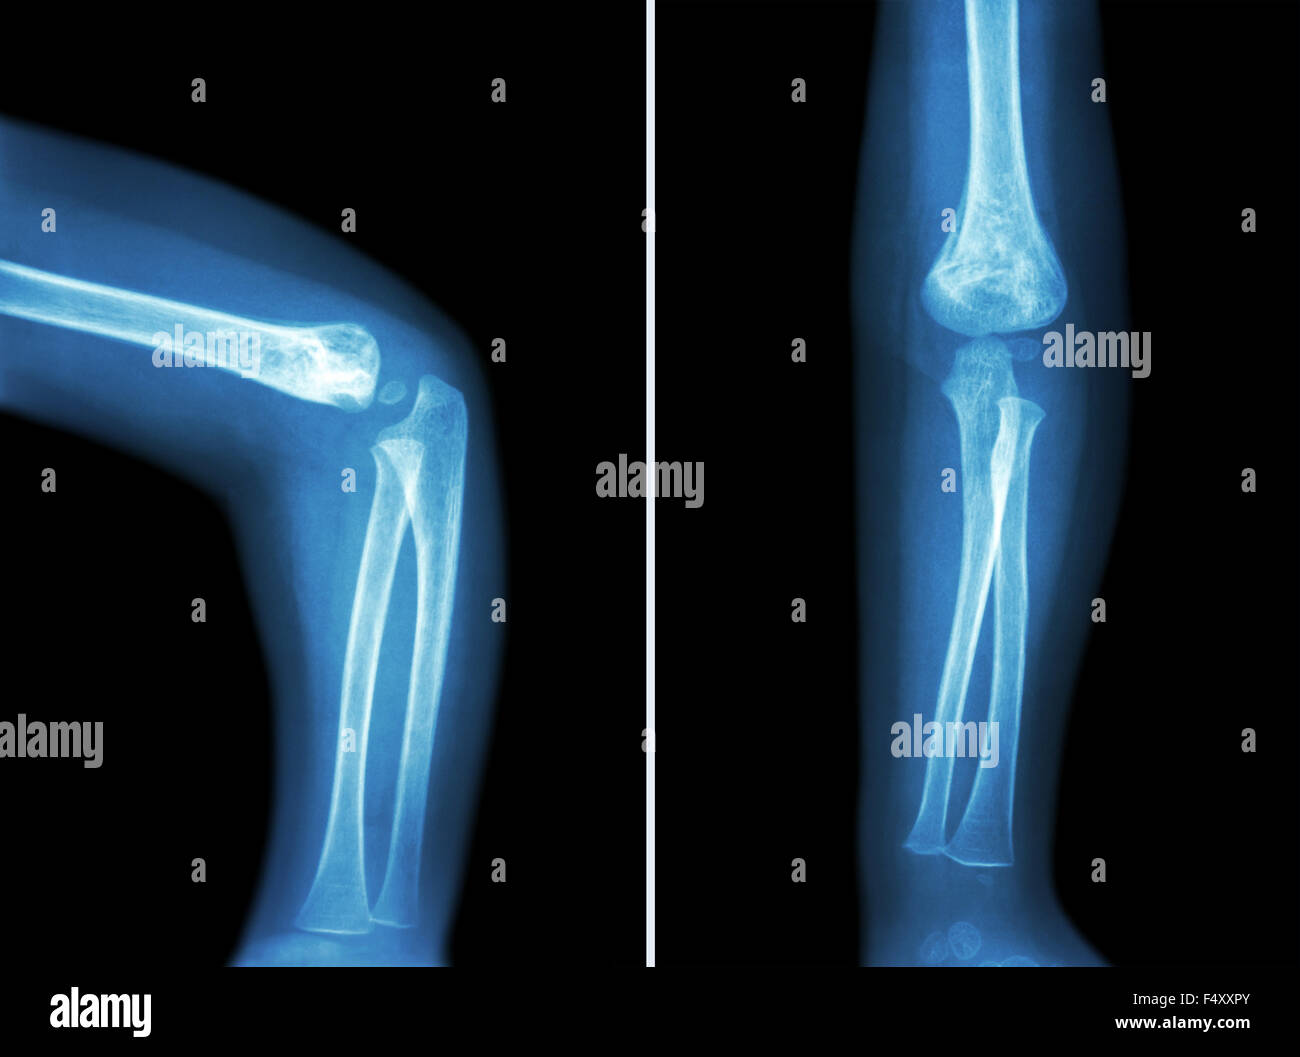

film xray elbow lateral show normal human's elbow Stock Photo Alamy Right Elbow Xray Normal Normal bones and joint alignment. visible anterior fat pad may be seen in normal patients and should only be thought of as an indicator of an elbow. Your technologist will return to reposition your elbow as needed. On the lateral image there is often a visible triangle of low density lying. The ap view should be. standard radiographic. Right Elbow Xray Normal.

Film xray of child 's elbow ( normal child 's elbow ) ( Side and front Right Elbow Xray Normal Your technologist will return to reposition your elbow as needed. On the lateral image there is often a visible triangle of low density lying. standard radiographic examination of the elbow includes anteroposterior (ap) and lateral views ( fig. visible anterior fat pad may be seen in normal patients and should only be thought of as an indicator of. Right Elbow Xray Normal.